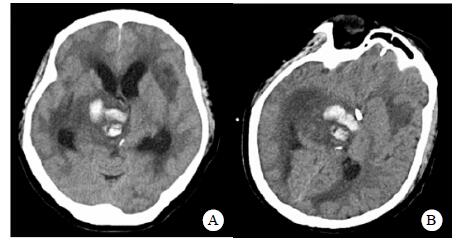

患者,女,54岁,工人,因“头晕5 d”于2019年9月29日至浙江大学附属第二医院急诊就诊。5 d前患者无明显诱因出现头晕,伴行走不稳、四肢乏力,无发热、咳嗽咳痰、胸闷气促、恶心呕吐、四肢抽搐等,未就诊。我院急诊头颅磁共振(MRI)示:右侧丘脑及左侧岛叶异常信号,局部累及右侧中脑(图 1),考虑脑多发占位性疾病。在急诊抢救室予甘露醇100 mL静滴脱水降颅压等对症治疗,5 h后患者逐渐意识模糊。急查血常规:白细胞16.1×109/L,中性粒细胞百分比73.4%;头颅CT示右侧丘脑、左侧岛叶病变,伴脑室扩张(图 2);急诊行“双侧脑室外引流术”,术中引流液呈淡血性。术后诊断:⑴(右侧丘脑)颅内占位性病变,脓肿首先考虑,肿瘤需排除;⑵脑积水;⑶脑疝。患者带气管插管转入ICU进一步治疗。当时体温38.3℃,脉搏99次/min,呼吸频率24次/min,血压169/87 mmHg(1 mmHg= 0.133 kPa),颈软,神志昏迷,右侧瞳孔3 mm,左侧瞳孔2.5 mm,对光反射迟钝。双肺呼吸音粗,可闻及少量啰音。左侧病理征阳性。患者3个月前曾因“反复胸闷气促伴发热1个月余”在本院风湿科住院,当时胸部高分辨CT示两肺间质性肺炎、下叶为著(图 3);血化验示血沉偏高,抗心磷脂抗体阳性;诊断为“间质性肺炎”,住院期间予甲泼尼龙40 mg/d静滴×8 d,60 mg/d静滴×6 d,共住院14 d;出院后予口服甲泼尼龙40 mg/d联合雷公藤多苷片每次20 mg,一日2次治疗;此后规范于本院门诊复诊。本次起病前2个月甲泼尼龙已减量至36 mg/d口服治疗。

| 右侧丘脑及左侧岛叶异常信号,局部累及右侧中脑 图 1 患者2019-09-29头颅MRI平扫+黑水成像 |